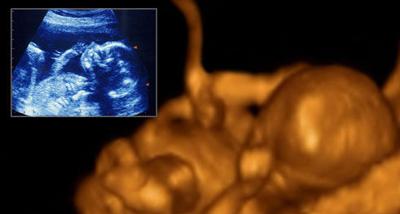

六个月:身长28-34厘米,体重约660克了。身体逐渐匀称。皮下脂肪的沉着进展不大,因此还很瘦,皮肤呈黄色。

八个月:身长为40-44厘米,体重达1500克左右。从这时起,羊水量不再象以前那样增加了。